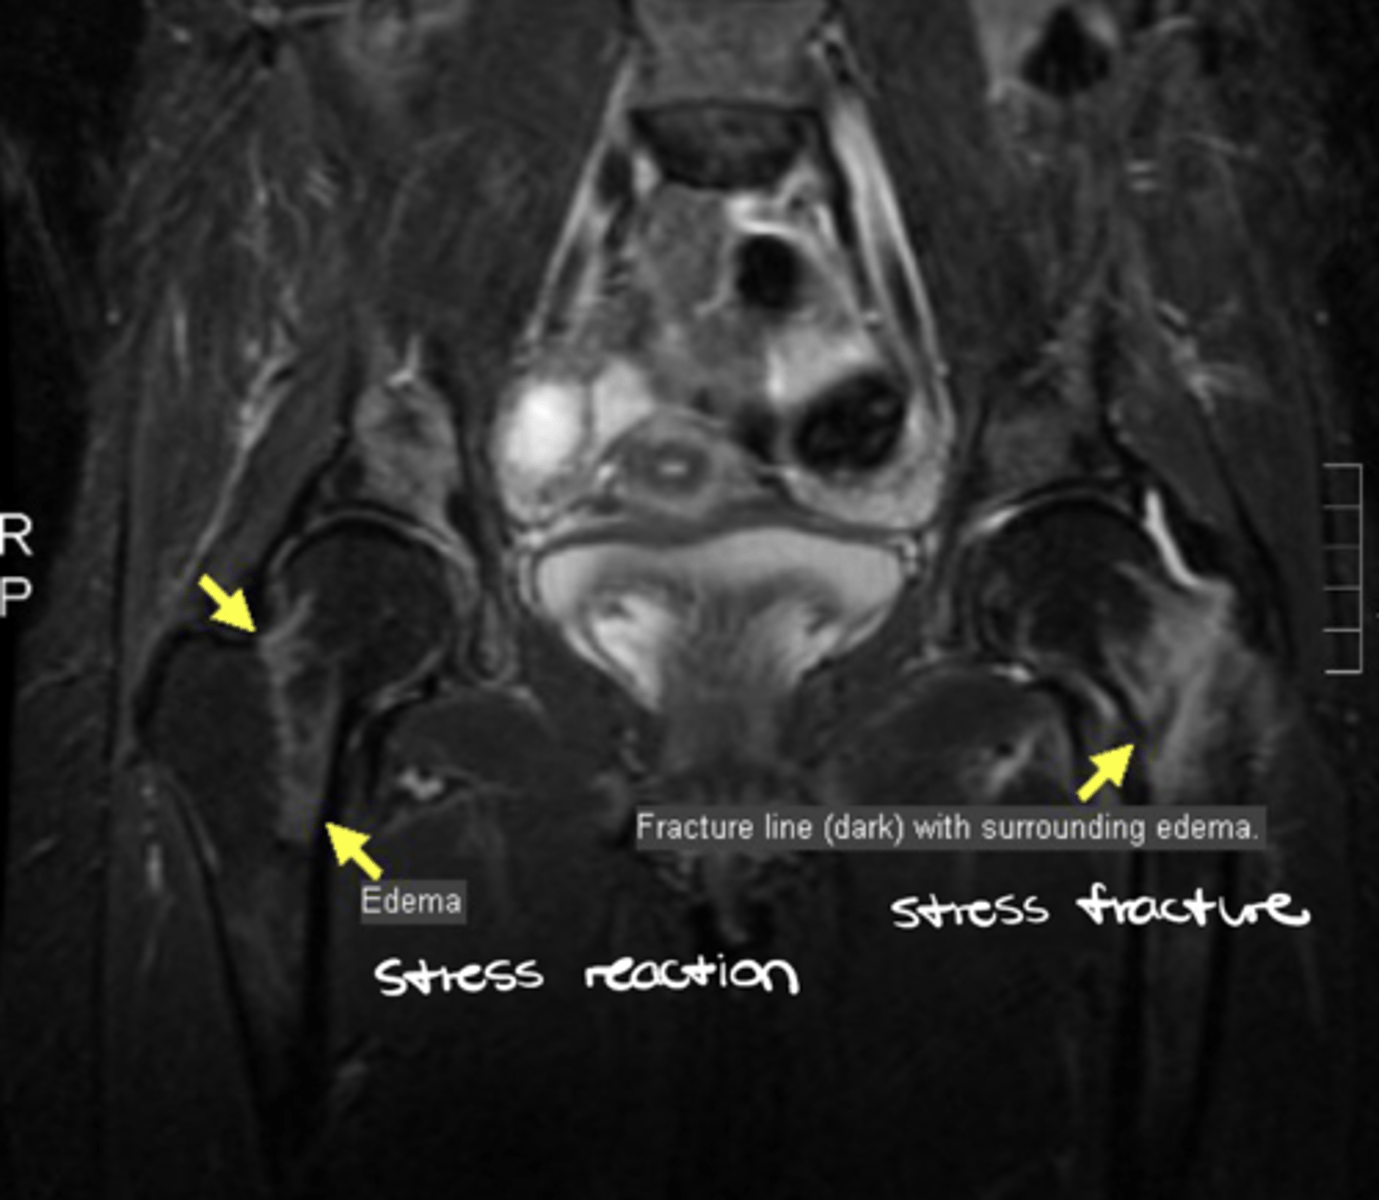

If the bone is normal and the bone breaks WITHOUT trauma, what is this known as?

Stress fracture

How do you ID a stress fracture?

1. History of activity induced symptoms

2. Standard radiograph initially normal

3. MRI shows abnormality much earlier (a band low signal on T1 and T2 + a zone of low (T1) and high (T2) signal)